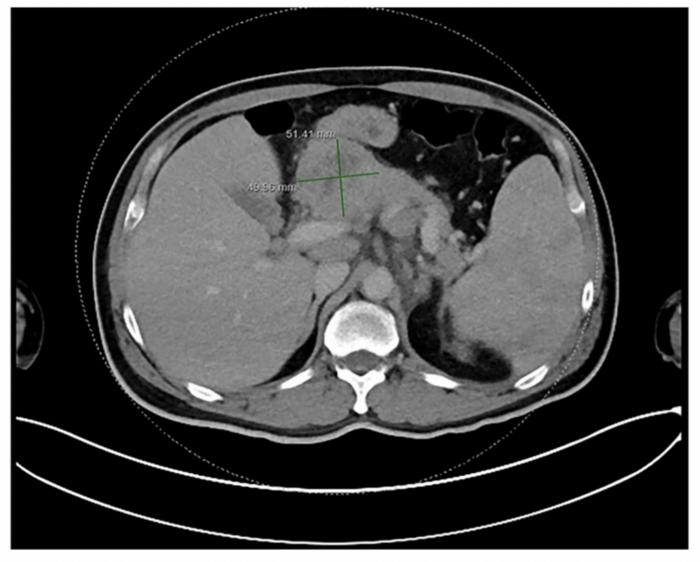

Imaging studies, predominantly contrast-enhanced computed tomography (CT), identified a substantial mass within the pancreatic parenchyma accompanied by adjacent peripancreatic lymphadenopathy. These radiological impressions initially heightened suspicion for adenocarcinoma; however, the absence of classic features such as ductal dilation or hallmark necrosis signaled the necessity for histological confirmation. Fine needle aspiration or core biopsy followed by immunohistochemical staining ultimately elucidated the neoplastic lymphoid population characteristic of nodular sclerosis Hodgkin lymphoma, thereby redefining the diagnostic landscape.